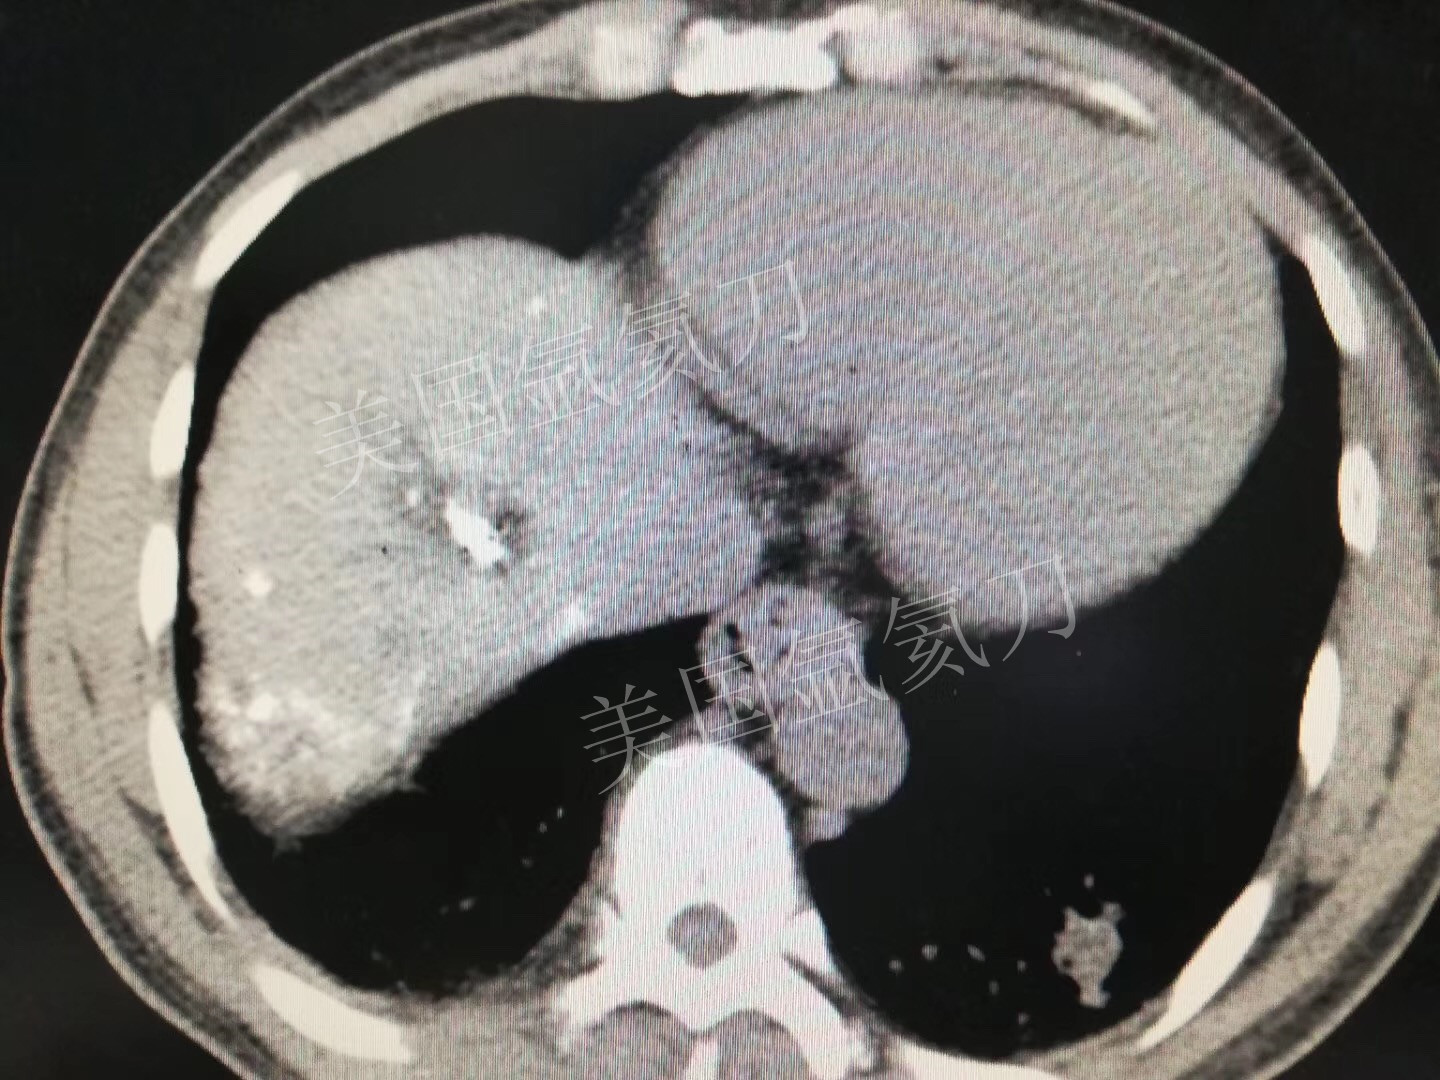

氩氦刀消融两个3公分介入后病灶,疗效确切!